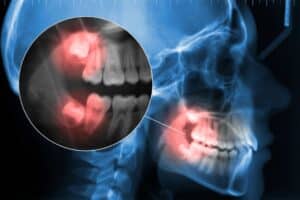

Ένας φρονιμίτης, γνωστός και ως τρίτος γομφίος, είναι πολύ πιθανό να προκαλέσει προβλήματα όταν παραμένει έγκλειστος ή ημιέγκλειστος μέσα στη γνάθο

Ένας φρονιμίτης, γνωστός και ως τρίτος γομφίος, είναι πολύ πιθανό να προκαλέσει προβλήματα όταν παραμένει έγκλειστος ή ημιέγκλειστος μέσα στη γνάθο. Η χειρουργική εξαγωγή ενός έγκλειστου φρονιμίτη γίνεται συχνά για να προστατευτούν οι δεύτεροι γομφίοι από βλάβες ή μετακινήσεις από τη πίεση που ασκείται. Μετά την εξαγωγή απαιτείται φροντίδα και σωστή επούλωση για την αποφυγή επιπλοκών.

Δυστυχώς, αυτό δεν συμβαίνει συχνά. Στην πλειονότητα των περιπτώσεων, η ανατολή τους παρεμποδίζεται λόγω έλλειψης χώρου στις γνάθους. Αυτό έχει ως αποτέλεσμα να παραμένουν έγκλειστοι (κάτω από τα ούλα ή το οστό) ή ημιέγκλειστοι (να προβάλλουν μερικώς στο στόμα).

Η σωστή κλινική και ακτινογραφική αξιολόγηση είναι καθοριστική για την απόφαση εξαγωγής. Ο γναθοχειρουργός ή ο οδοντίατρος εξετάζει:

Τη θέση του φρονιμίτη μέσα στη γνάθο

Τη σχέση με σημαντικές ανατομικές δομές, όπως το κάτω φατνιακό νεύρο ή το ιγμόρειο άντρο

Την παρουσία φλεγμονής, κύστης ή πόνου

Η πανοραμική ακτινογραφία ή η αξονική τομογραφία (CBCT) δίνουν την πλήρη εικόνα για τον σχεδιασμό της επέμβασης.